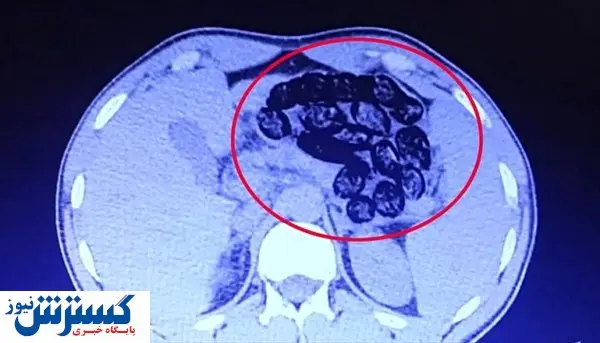

پلیس ترکیه دو شهروند ایرانی که ۹۲۰ گرم مواد مخدر را در قالب ۱۰۳ بسته در معده خود حمل می‌کردند تا از شهر وان به ازمیر بروند دستگیر کرد.

پلیس ترکیه پس از دستگیری این افراد، آنها را به بیمارستان منتقل کرده و ۹۲۰ گرم مواد مخدر موجود در معده آنها خارج شد.